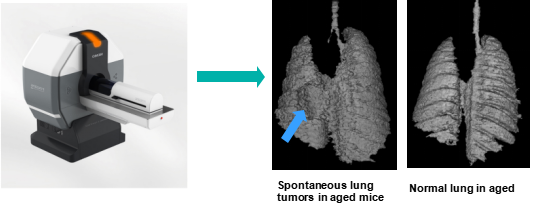

据研究发现,FVB品系老龄鼠自发肺部肿瘤概率高,为提高药物临床转化成功率,我们利用Micro-CT平台对FVB品系老龄鼠进行扫描,并建立了完整的、高通量的小鼠肺癌筛查、诊断和药物药效评价方案。

01.Micro-CT 小动物肿瘤筛查平台

小动物CT是临床前药物研究的重要工具,可以纵向提供有价值的疾病进展和治疗信息。可广泛应用于骨骼研究、生物材料研究与开发、肿瘤与心血管疾病机理研究与评价、新药开发等领域。

我们建立的Micro-CT高通量筛查平台可以在短时间内实现小型啮齿动物(小鼠或大鼠)体内的结构成像,以及对离体动物组织、生物材料等样品的无损三维检测。

高通量扫描模式下,扫描仓可以同时容纳6只小鼠,扫描精度满足后续分析需求,可用于高通量筛选及分析。